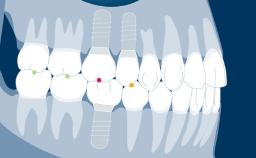

Prosthodontically driven implant planning ensures that implant placement is compatible with the desired end result, which is a key factor for successful outcomes in implant therapy.

Digital technologies now available in the field of implant dentistry facilitate prosthodontically driven implant planning. Benefits of these technologies include significant improvements in patient assessment and treatment planning, allowing clinicians to position supporting implants with a high degree of accuracy.

- define the general concepts and terminology used in computer-aided planning

- discuss the indications for using computer-aided planning